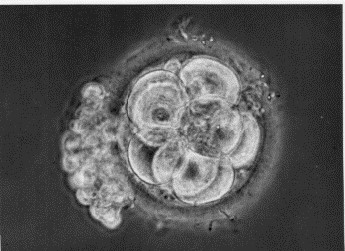

University of Cambridge research fellow, Marta Shahbazi, discusses developments in IVF research making it possible to grow human embryos in vitro for longer than ever.

Connie Orbach, curator of new exhibition IVF: 6 Million Babies Later, explores the pioneering work of Jean Purdy, a central figure in the development of IVF.

Professor Martin Johnson explores the difficulties experienced by physiologist and Nobel laureate Bob Edwards in his pioneering IVF work.